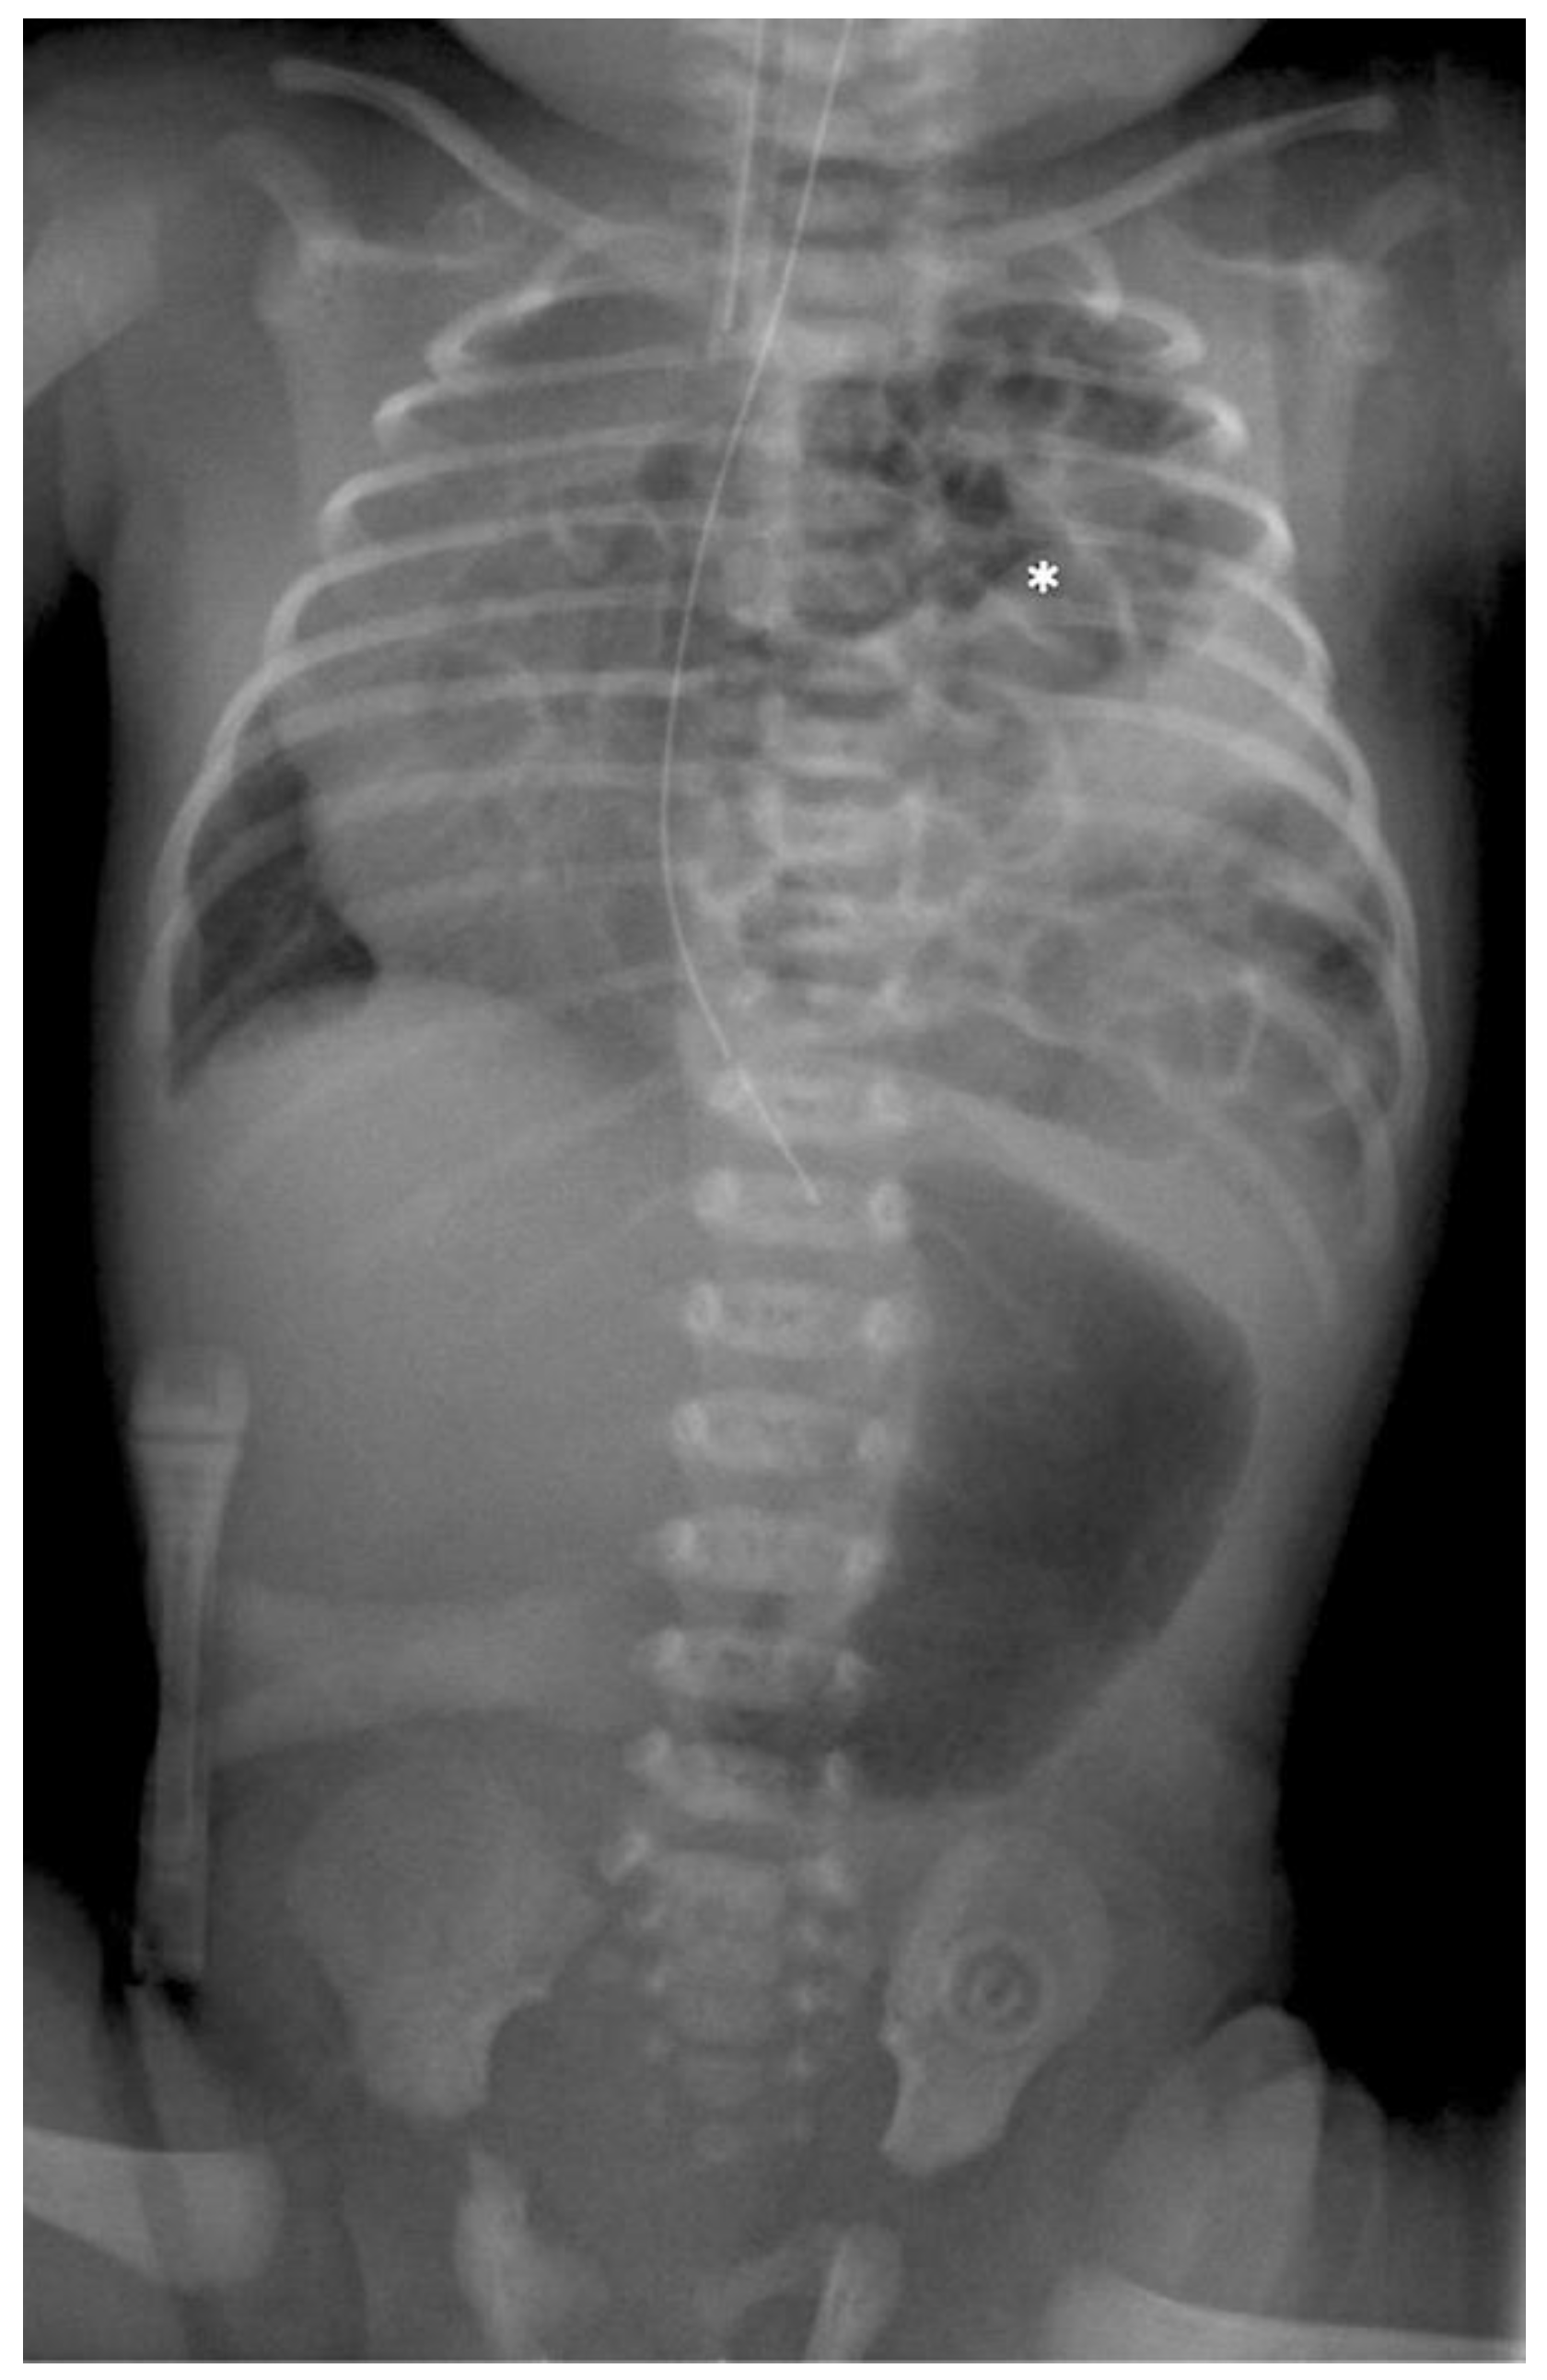

Postoperative follow-up: All patients left our operation room intubated and in cardiorespiratory stable condition. The mean ventilation time after operation including weaning was 75.8 h (range 25.5–132 h). The mean length of hospital stay was 19 days (range of 7–33 days). Postoperative clinical follow-ups were performed 2 and 6 months after hospital discharge with plane X-ray images (see Figure 7). Further follow-up examinations were performed every six months up to two years of age, thereupon, they were performed every year. Today, the mean follow-up time is 3.5 (1.1–6.3) years but in the future, the number will grow. Each patient was seen on average 5 (3–9) times after discharge and they remain in our follow-up schedule. The outcome of all seven patients to date was excellent, we had no recurrent hernias, no scoliosis, and no cases of intercostal neuropathy.

Figure 7. Radiograph of the same patient after 6 months.